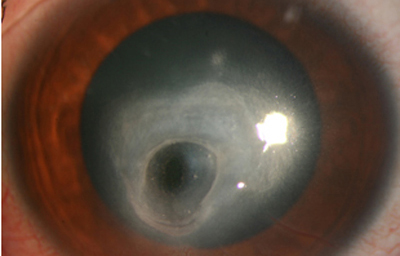

En su evolución se observará aumento del edema, agrandamiento y coalescencia de los infiltrados formando un anillo, (Figura 9, 10 y 11) que progresa hacia la formación de un absceso (Figura 12, 13 y 14), queratolisis superficial, adelgazamiento y perforación corneal (Figura 15 y 16).

Fig. 12 Síntomas de 15 días evolución

Fig. 13 Síntomas de 15 días evolución

Fig. 14 Síntomas de 15 días evolución